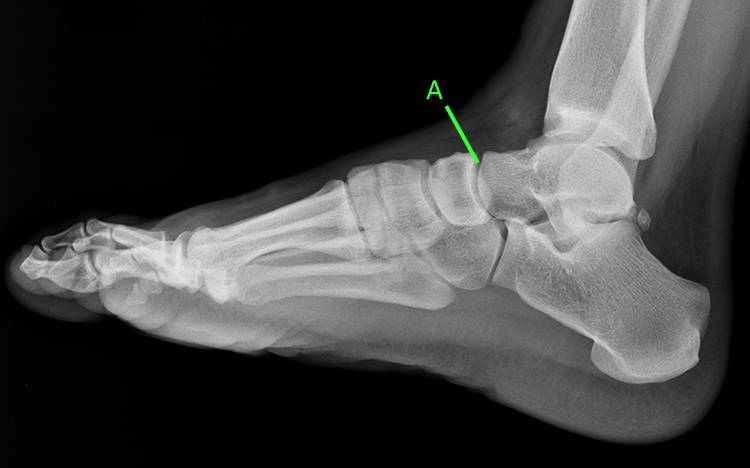

СКЛАДНИЙ СУГЛОБ (ЯК ВИЛКА). Є ВСІ ПЕРЕДУМОВИ ДЛЯ РОЗТЯГНЕННЯ ЗВ'ЯЗОК І ЗМІЩЕННЯ КІСТОК. РОЗПІЗНАЙТЕ СУГЛОБ.

варіанти відповідей

СУГЛОБ УТВОРЕНИЙ СУГЛОБОВИМИ ПОВЕРХНЯМИ ЛАТЕРАЛЬНОЇ І МЕДІАЛЬНОЇ КІСТОЧКИ ТА ТІЛОМ ТАРАННОЇ КІСТКИ. РУХИ НАВКОЛО ФРОНТАЛЬНОЇ ОСІ. ЧАСТО - РОЗТЯЖІННЯ, ВИВИХИ, РОЗРИВИ, ПЕРЕЛОМИ. РОЗПІЗНАЙТЕ СУГЛОБ.

КОЛІННИЙ С.

ГОМІЛКОВО-СТОПНИЙ С.

КУЛЬШОВИЙ С.

ЛІКТЬОВИЙ С.

ПЛЕЧОВИЙ С.

ПРОМЕНЕВО-ЗАП'ЯСТКОВИЙ С.

Запитання 78

ЯКА КІСТКА Є "МЕНІСКОМ" У СУГЛОБІ ЩО СПОЛУЧАЄ ГОМІЛКУ І СТОПУ?

НАДП'ЯТКОВА К.

П'ЯТКОВА К.

ЧОВНОПОДІБНА К.

КУБОПОДІБНА К.

КЛИНОПОДІБНА К.

FIBULA

TIBIA

ГОРОХОПОДІБНА К.